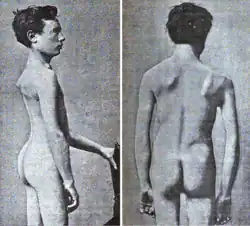

| 1861 | Person with muscular dystrophy depicted by Duchenne. Based on the muscles involved, this person could have had FSHD. |

| 1884 | Landouzy and Dejerine describe a form of childhood progressive muscle atrophy with characteristic involvement of facial muscles distinct from pseudohypertrophic (Duchenne's MD) and spinal muscle atrophy in adults.[128]

Two brothers with FSHD followed by Landouzy and Dejerine Photograph of one brother at age 21. The right scapula is protracted, downwardly rotated, and laterally displaced. Drawing of another brother at age 17. Visible is lumbar hyperlordosis. The upper arm and pectoral muscles appear atrophied. |